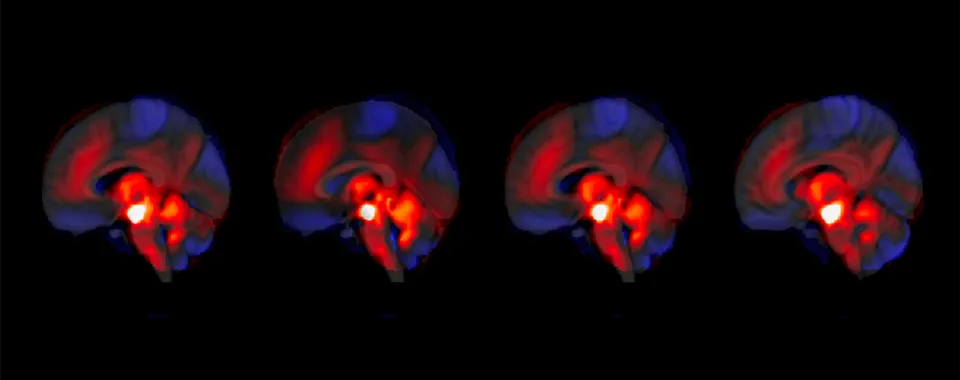

Image d’illustration de la connectivité entre le cervelet et l'ATV. (Indrit Bègue et al., 2025) © Thomas Bolton

Grâce au suivi de 146 patients et patientes, sur une période allant de 3 à 9 mois, ainsi qu’à l’analyse d’une cohorte indépendante de validation, l’équipe a observé et décrit pour la première fois l’interconnexion entre le cervelet et l’ATV dans le contexte de la schizophrénie. «Nous montrons qu’une régulation renforcée du cervelet sur le système de récompense s’accompagne d’une atténuation des symptômes négatifs et inversement. Ce mécanisme inédit ouvre des perspectives pour développer des approches thérapeutiques ciblées», explique Jade Awada, doctorante dans l’équipe d’Indrit Bègue, au Laboratoire de neuroimagerie et psychiatrie translationnelle du Département de psychiatrie de la Faculté de médecine de l’UNIGE ainsi qu’au Centre Synapsy de recherche en neurosciences pour la santé mentale, première auteure de l’étude. Ces analyses ont été réalisées par Jade Awada et Farnaz Delavari, co-première auteure de l’étude et chercheuse dans le laboratoire du Pr Stephan Eliez.